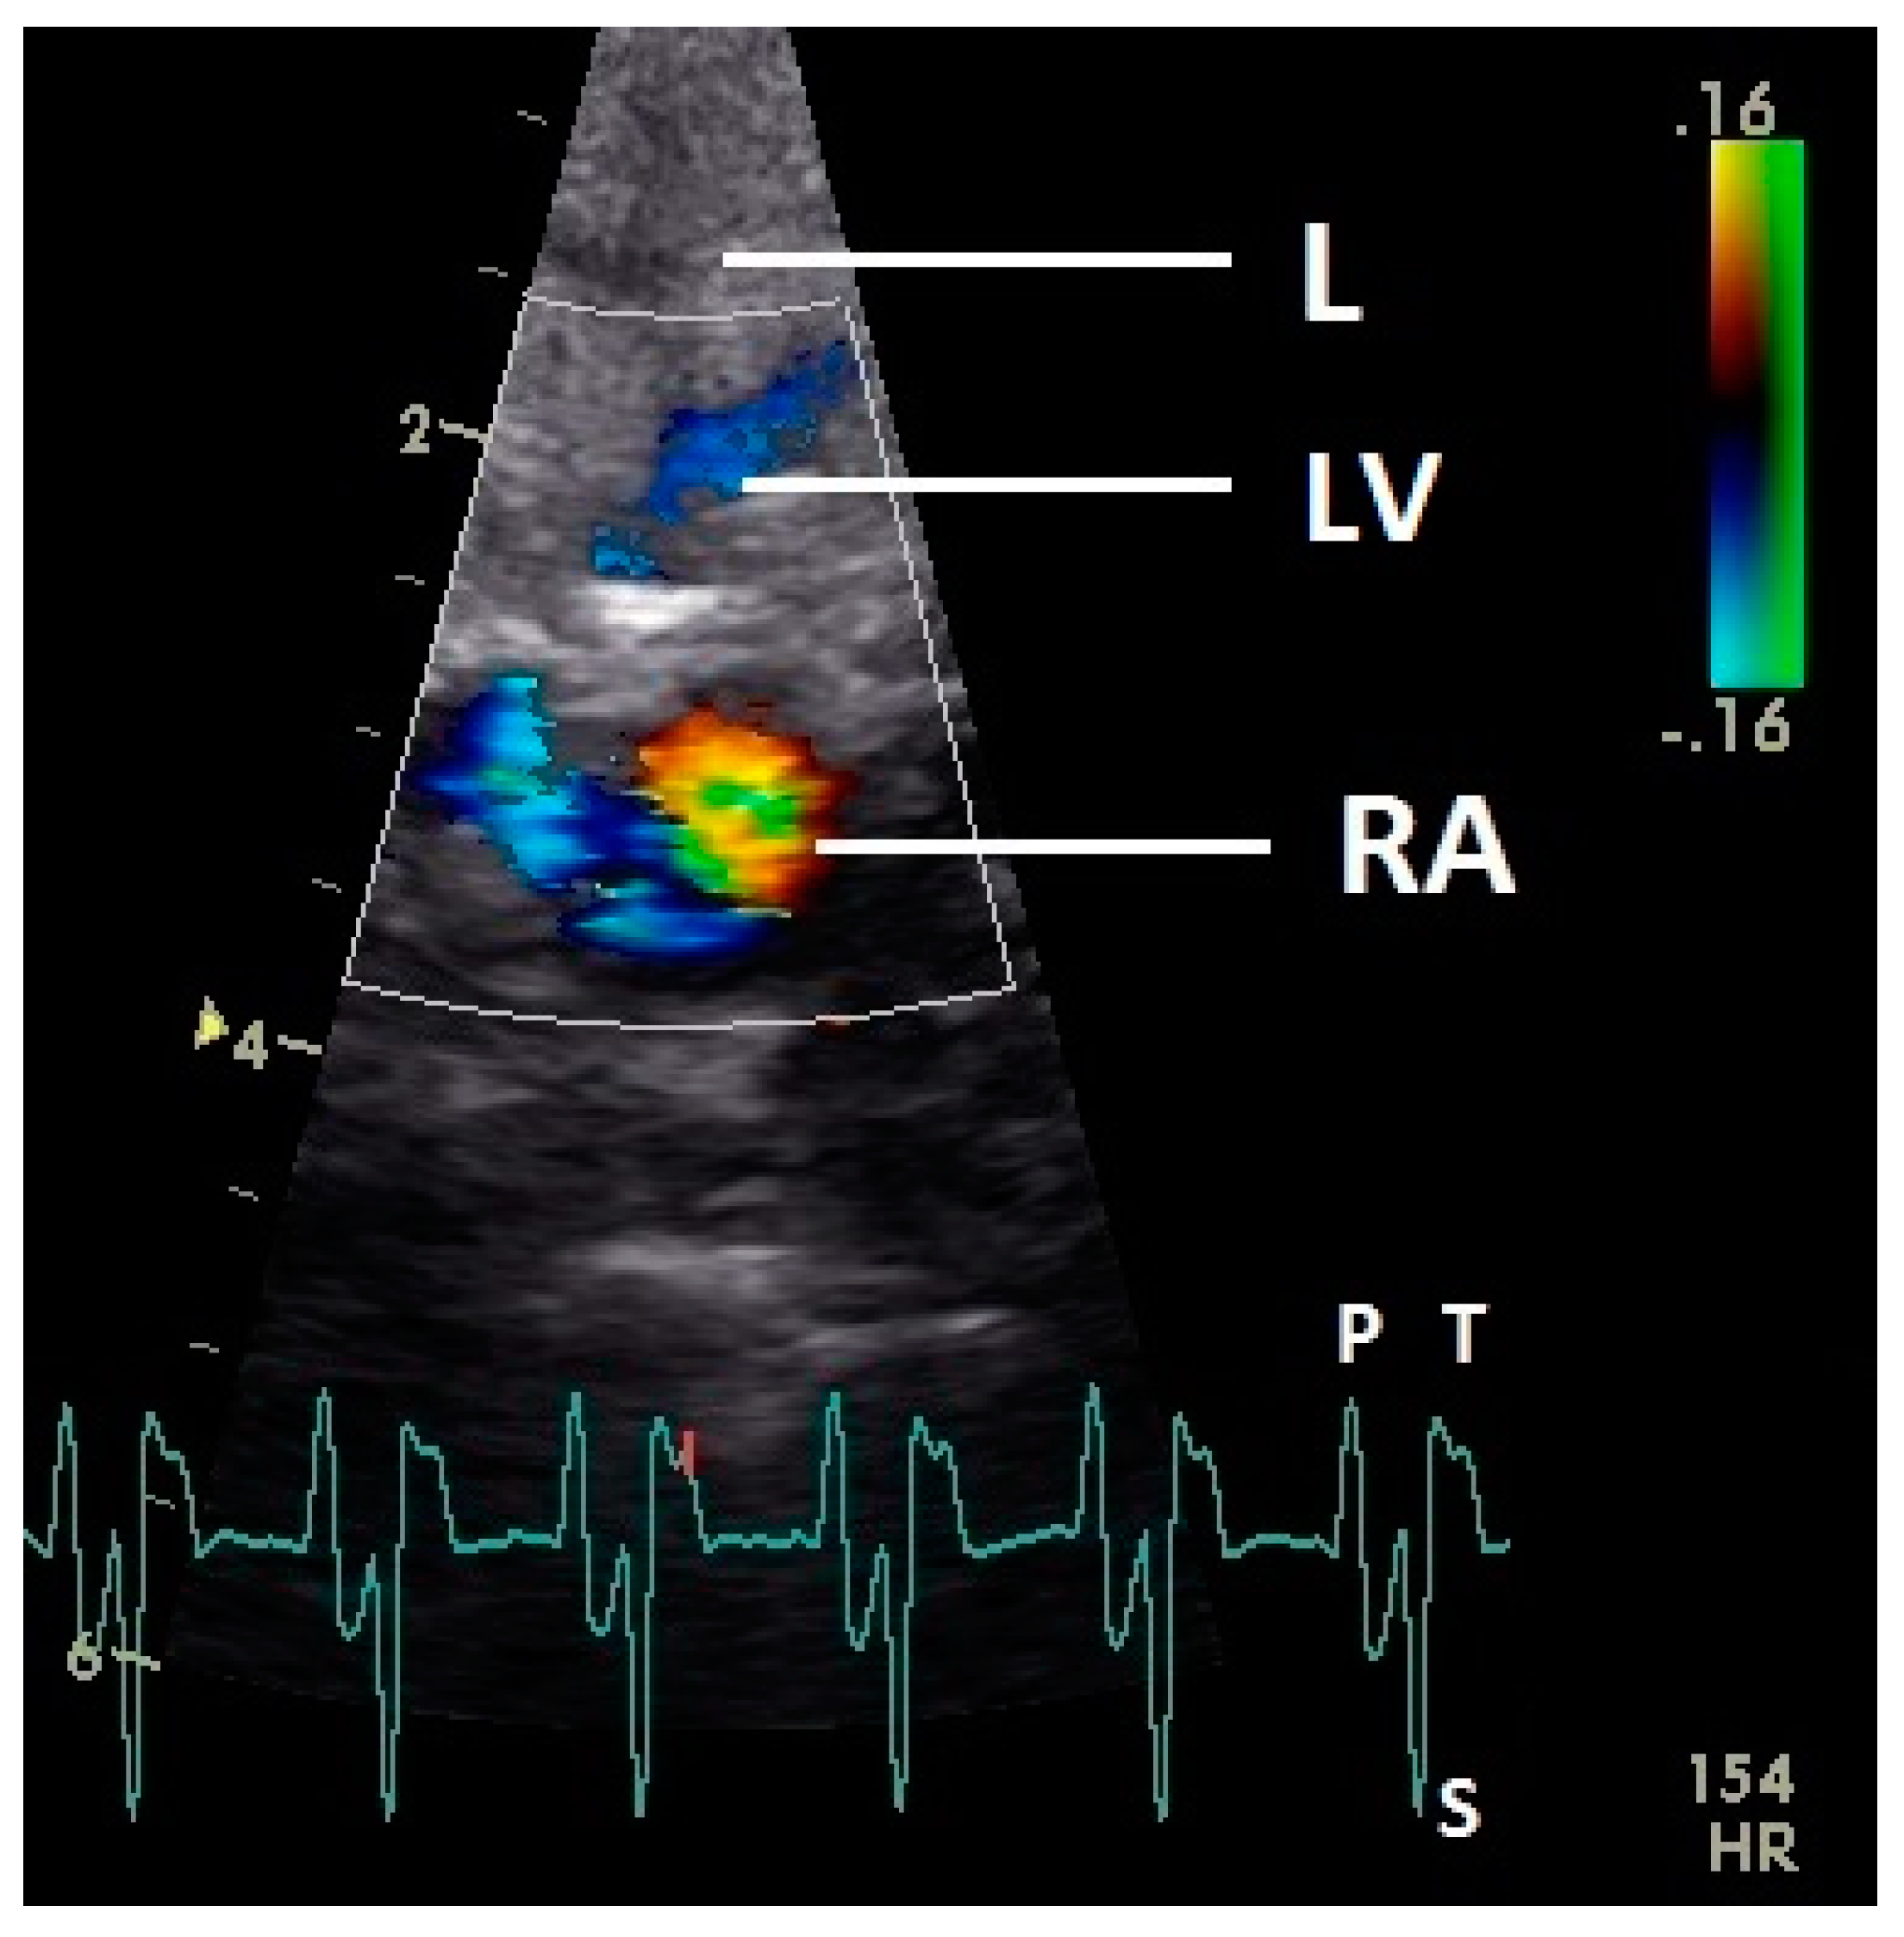

The blood flow in the right atrium was observed in 35 pigeons and was difficult to examine with our settings. After the P wave of the ECG in the phase of the relaxation of the myocardium of the right atrium, a blue filling signal in 15 pigeons (34.9%) was visualized. In the second half of the systole (T wave) a late blue filling inflow signal in the atrium was seen in 35 pigeons (81.4%); at this time a blood flow in the liver veins was also observed (Figure 9). Simultaneously to the blue inflow signal a red blood flow signal in the area of the septum in the right atrium was observed (Figure 9).

Figure 9.

Color Doppler image of the late blood inflow in the right atrium (blue signal). The vortex formation of the blood flow in the atrium (red and blue signal simultaneously) and the blood flow in the liver vein (LV; blue signal in liver tissue) are visible. RV: right ventricle; RA: right atrium; HR: heart rate. Electrocardiogram: P: P wave, S: S wave, T: T wave. The color scale on the right of the image is calibrated in m s−1.